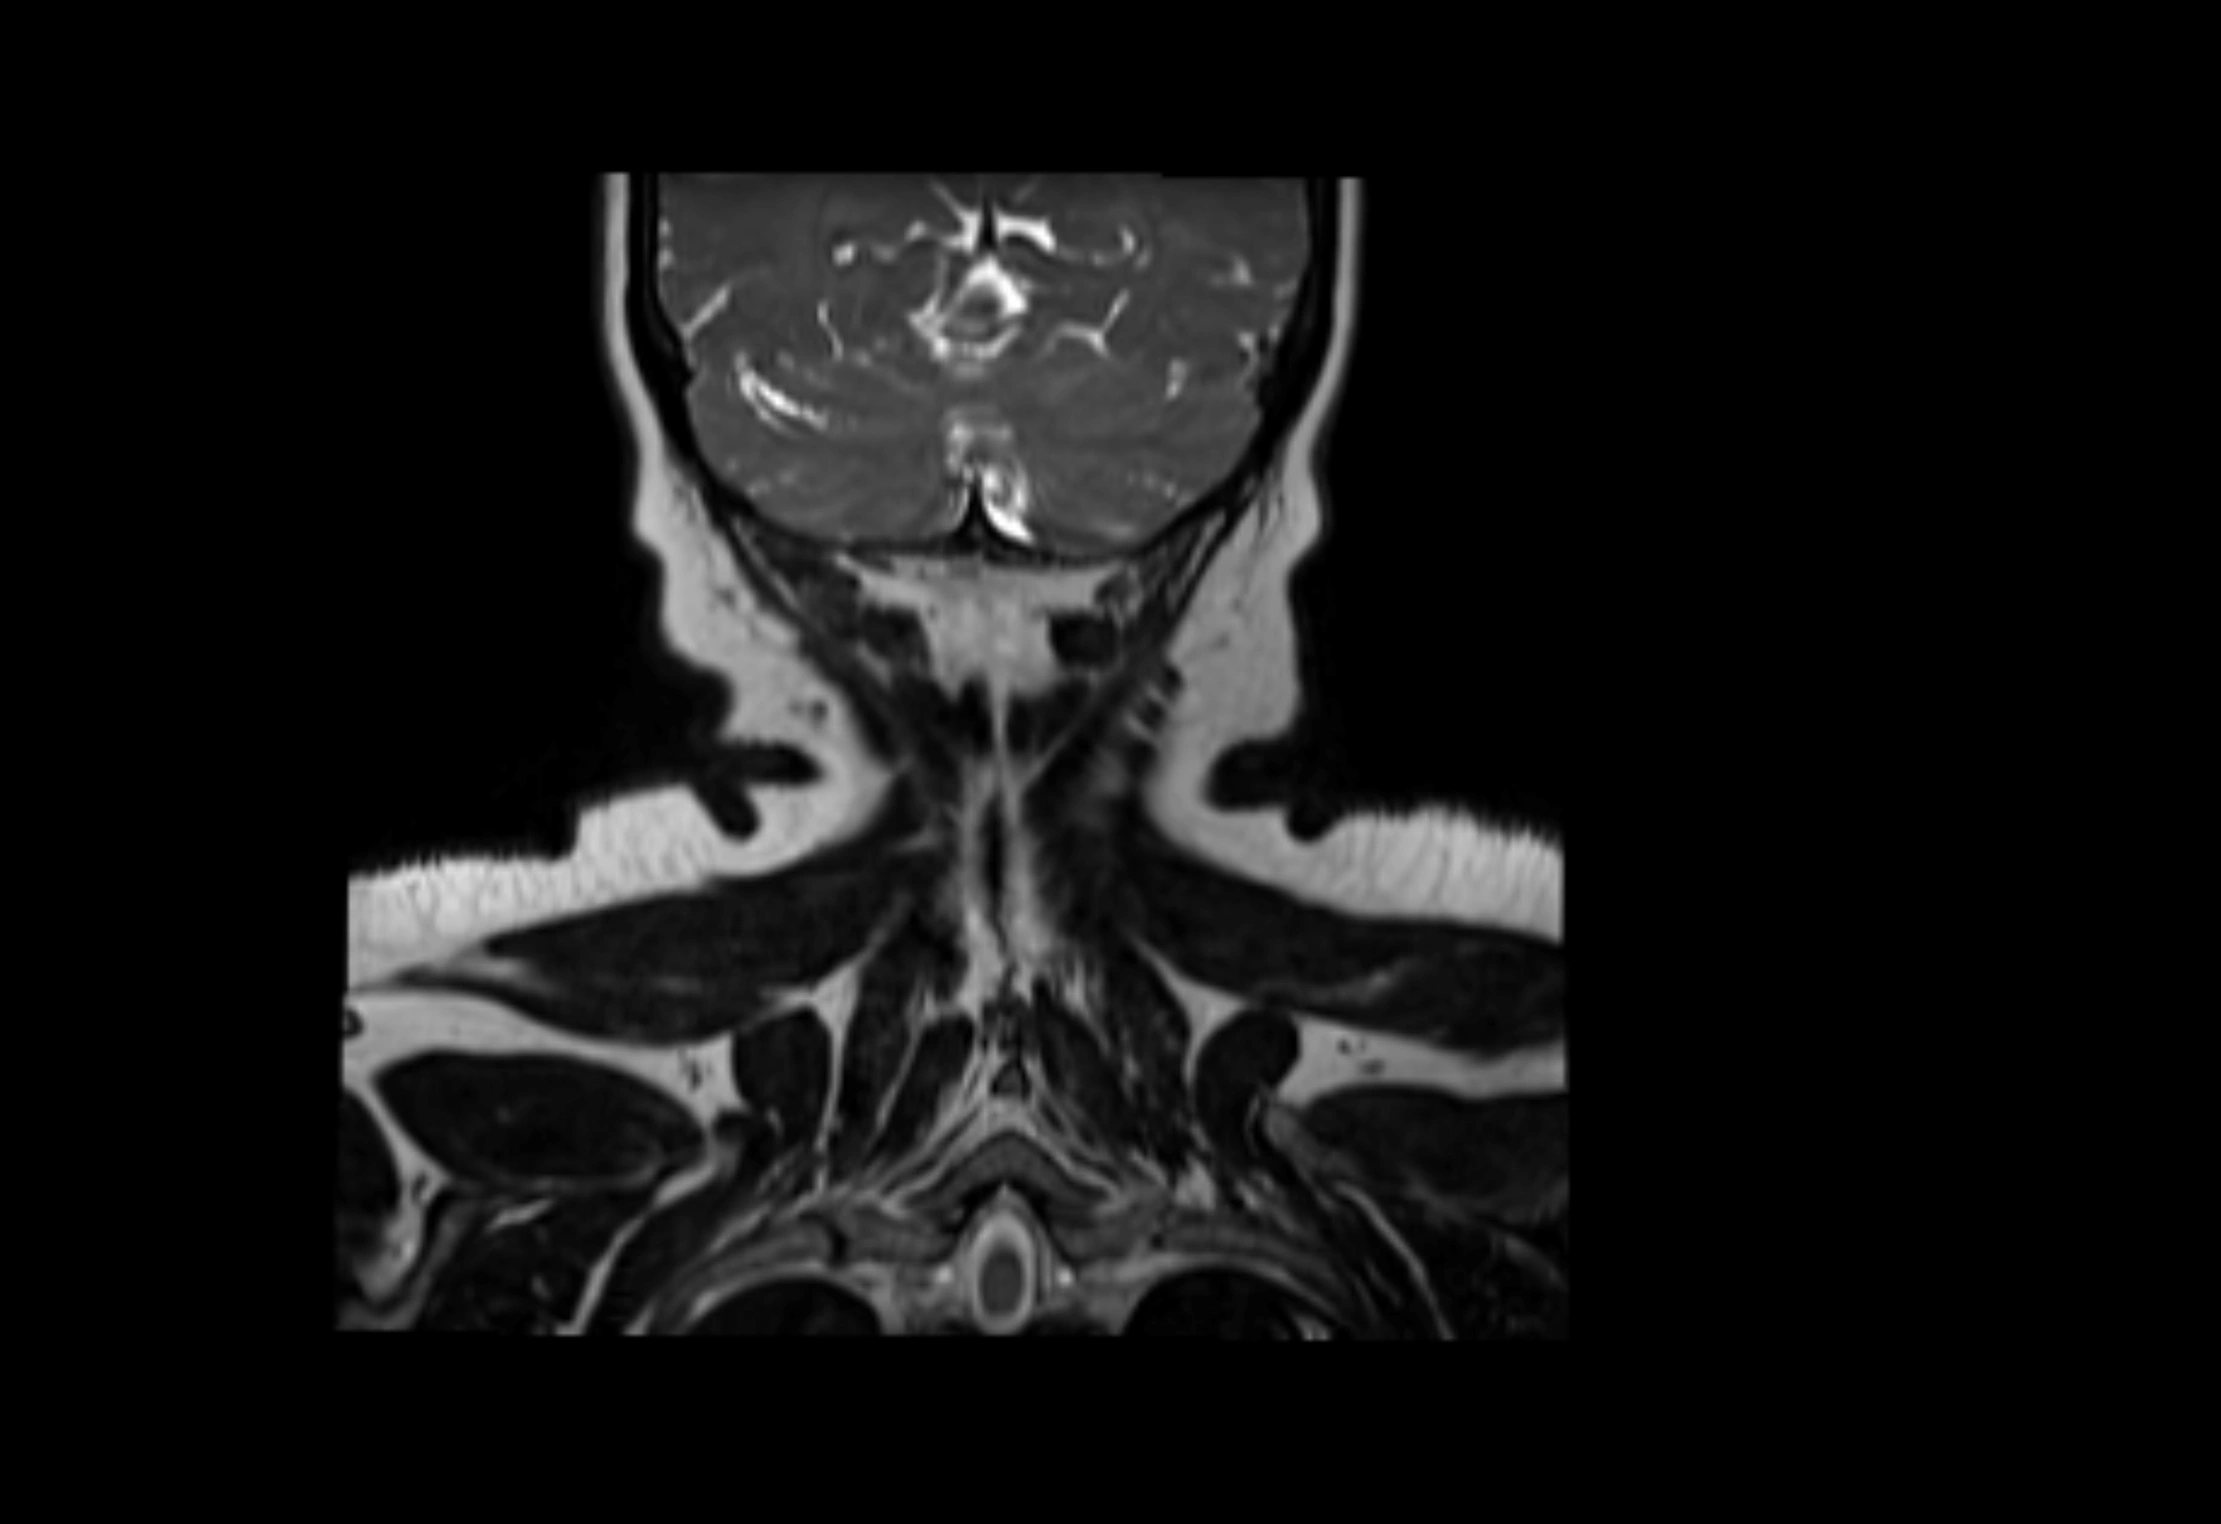

Accessory lymph nodes are small, secondary lymph nodes located along the main facial and cervical lymphatic chains, often adjacent to primary lymph nodes, such as preauricular, submandibular, or occipital nodes. They are typically less than 5 mm in diameter, embedded within subcutaneous fat or connective tissue, and may be variable in number and location. These nodes provide additional filtration and immune surveillance for lymph collected from the face, scalp, and neck regions. Accessory lymph nodes are usually non-palpable in healthy individuals but may enlarge in response to infection, inflammation, or metastasis, making them clinically significant.

Location

• Found along primary lymph node chains, including preauricular, submandibular, parotid, and occipital regions

MRI Appearance

T2-weighted images:

• Nodes show intermediate signal, with surrounding fat bright

• Useful for detecting edema, inflammation, or infiltration

• Fatty hilum may appear slightly hyperintense relative to cortex